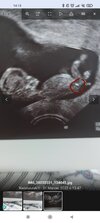

100% chlopak( usg)?Jak myslicie?

Jeśli ta biała jaśniejsza kreseczka to wyrostek, to bardziej wskazywałoby to na dziewczynkę.

Ale ja nie jestem lekarzem, więc nie ma pewności czy ta kreseczka to wyrostek 😂

To masz na mysli co zaznaczylam w koleczku? Kurka nawet nie zauwazylam tego wczesniej i faktycznie tutaj " to cos" jest skierowane ku dolowi🤔dalas mi do myslenia

... Bo ja to bardziej szukalam czegos sterczacego lub plaskiego wzdlug kregoslupa...ale tutaj ewidentnie na kazdym zdjeciu jest chyba zasloniete nozkami... Ale kurcze faktycznie...ta biala struktura ( kreseczka o ktorej mowisz) jest konkretnie wyodrebniona i zwrocona ku dolowi. Teraz mam do myslenia😃. Powiem Ci, ze jestes bardzo spostrzegawcza. Choc ponoc ja do takowych naleze😃a kurna w ogole na to nie spojrzalam...a teraz jak powiedzialas to tylko to widze😆

Tak - to miałam na myśli. Ale czy to jest ten wyrostek płciowy, to nie mam pojęcia.

Na zdjęciach w necie nieco inaczej wygląda - bardziej cienka na linia jest.